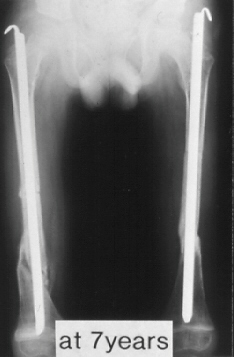

A 18-years-old boy. Body height 114cm. Sillence type III.

The first visit was at 4 years of age. He sustained 16 fractures in L/E and 30 fractures in U/E. He underwent 9 operations. He had 80 degrees progressive scoliosis and recently underwent posterior spinal fusion with internal instrumentation. He obtained his initial gate at 18 months of age, and had been practical ambulator until 9 years old. However, the diameter of the femur which was 15mm at 7 years of age had started to decrease prior to the functional aggravation. He eventually became a non-ambulator after the ankle joint fracture at 9 years old. The diameter of the right and left femur at the age of 18 were 7 and 8 mm respectively.